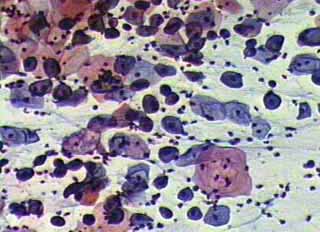

κυτταρολογικών επιχρισμάτων κατά Papanicoloau και η συσχέτιση τους με το ιστορικό

Το ενδιαφέρον του κλινικού γυναικολόγου στο πόρισμα του κυτταρολογικού επιχρίσματος του τραχήλου της μήτρας, περιορίζεται συνήθως στο συμπέρασμα του, σχετικά με την ύπαρξη κάποιας δυσπλασίας ή έστω φλεγμονής, στην περιοχή.

Ωστόσο ακόμη και το λεγόμενο ‘’φυσιολογικό’’ επίχρισμα, μπορεί να μας δώσει μία επί πλέον αξιόλογη πληροφόρηση, αν τα ευρήματα του ενταχθούν σωστά από τον κλινικό γιατρό, τόσο στην χρονική συγκυρία, όσο και στο ιστορικό, ή στα κλινικά, κολποσκοπικά και υπερηχογραφικά ευρήματα.

Η γενικότερη γυναικολογική οπτική γωνία, στην ερμηνεία ενός κυτταρολογικού πορίσματος, είναι αρκετά σημαντική για την αξιολόγηση άλλων προβλημάτων, πέραν των δυσπλασιών.

Οι εικόνες και τα πορίσματα που επιδεικνύονται, είναι τυχαία ευρήματα ενός απογευματινού ιατρείου.